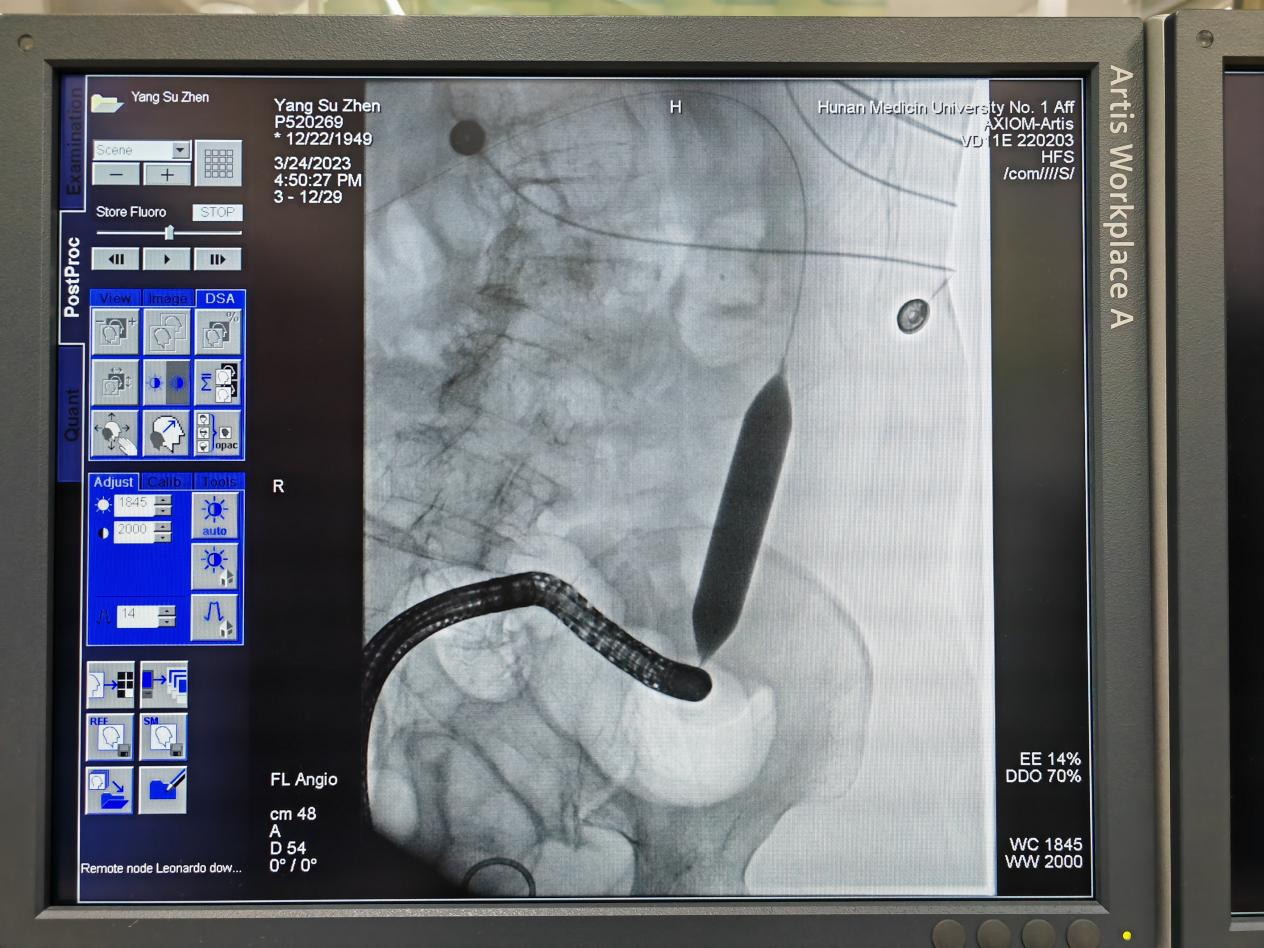

科室在怀化市率先开展以双套管冲洗负压引流为基础的肠瘘综合治疗技术,该技术引进于东部战区总医院,已成功救治众多术后肠瘘患者。同时,通过内镜下肠梗阻导管置入、内镜联合介入下肠道支架置入等先进医疗技术,为各类肠梗阻患者提供优选诊疗方案。

降结肠癌并梗阻行肠道支架植入解除梗阻